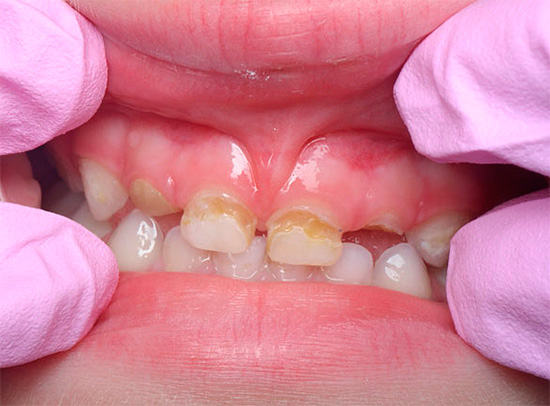

La carie cronica può essere osservata anche nei denti primari. Questa è una delle malattie più comuni nei bambini, poiché può essere difficile per i genitori tenere traccia delle condizioni dei loro denti in tenera età. A volte il dentista deve affrontare i problemi del decorso acuto della carie, quando in pochi mesi la carie del bambino nella fase spot si trasforma in profonde violazioni del tessuto dentale. In questo caso, è necessario interrompere immediatamente il suo sviluppo conducendo un trattamento complesso di tutti i fuochi.

Un aspetto tipico dei denti con carie cronica è mostrato nella foto qui sotto:

Non ci sono lesioni estese dei denti e in alcuni punti le aree scure sono di dimensioni molto ridotte e spesso non attirano l'attenzione del paziente. Di solito il dolore è assente.

- La carie media cronica è caratterizzata da un'ampia cavità che colpisce la dentina. In questo corso, la cavità non ha ammorbidito la dentina, ma solo pigmentata dentina cariata. Il fondo è denso con lievi sporgenze e rugosità, che indica un processo lento nella fase di compensazione a causa della sostituzione della dentina.

- La carie cronica profonda differisce dalla media solo per la profondità della cavità. Inoltre non ha bordi a smalto sporgenti, generalmente ben lucidati.